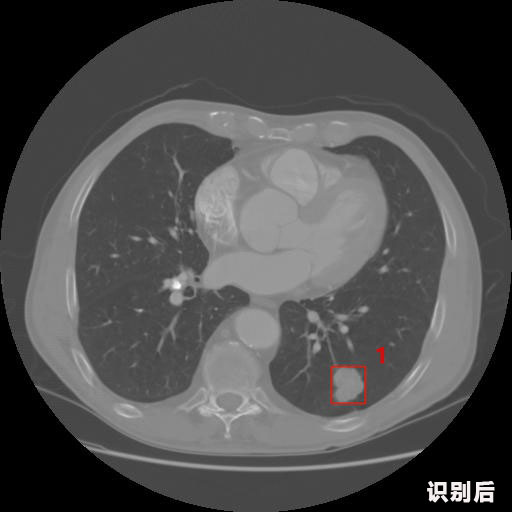

英特健康AI深度学习医疗图像识别系统案例_胸部CT

04.jpg

报告:

1.发现肺结节的可能性为95.56%---位于框指数位置:[331.70554 366.13406 365.21707 403.96234]